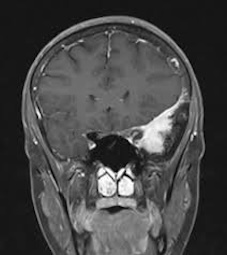

The Brain Tumor MRI Images dataset is a publicly available dataset on Kaggle555https://www.kaggle.com/datasets/sartajbhuvaji/brain-tumor-classification-mri/data. It contains MRI images of human brains divided into four categories: No Tumor, Pituitary Tumor, Benign Tumor, and Malignant Tumor. For our study, we selected three categories: No Tumor (NT), Benign Tumor (BT), and Malignant Tumor (MT). From each category, we chose three MRI images representing different parts of the brain that best illustrate the characteristics of each class. The categories included in this study are described as follows:

The Benign Tumor (BT) category includes MRI images showing non-cancerous tumors in the brain. Benign tumors grow slowly and do not spread to other parts of the brain or body. While generally less dangerous than malignant tumors, they can still cause symptoms if they press on surrounding brain tissue. Accurate identification of benign tumors is important for planning appropriate treatment, which may involve monitoring, minor surgery, or other non-aggressive interventions.

The Malignant Tumor (MT) category consists of MRI images showing cancerous tumors. These tumors are aggressive, can grow rapidly, and may spread to other parts of the brain or body. Malignant tumors require immediate and intensive treatment, such as surgery, chemotherapy, or radiotherapy. Differentiating malignant tumors from benign tumors is crucial, as it directly impacts the treatment strategy and can significantly affect patient outcomes.

Differentiating these categories is essential for early detection, accurate diagnosis, and effective treatment planning. By distinguishing between healthy brains, benign tumors, and malignant tumors, medical professionals can identify abnormalities more reliably, reduce misdiagnoses, and streamline medical care. In this study, we apply our divergence measure to differentiate between the selected MRI images, as illustrated in Figure 5. In Figure 5, the first row shows MRI images from NT patients, the second row shows images from BT patients, and the third row shows images from MT patients.

Using the divergence measure, we calculated estimates for each pair of MRI images and compared the three categories. For calculation, each grayscale image is represented by its pixel intensity values (scaled to [0,1]). These values are flattened into a one dimensional vector and used as the sample data for subsequent analysis. For any two images, denoted data1 and data2, we then computed an empirical based divergence estimate. The resulting values are presented in Tables 4, 5, and 6. A higher value of the divergence estimate indicates a greater likelihood of a tumor. These results demonstrate that the divergence measure can serve as an effective tool for detecting tumors in medical image data.

Table 4. Estimated Divergence Measure Values for Pairs of Different Classes in Axial View Brain MRIs

NT1 BT1 MT1

NT1 0 0.037 0.049

BT1 0.037 0 0.012

MT1 0.049 0.021 0